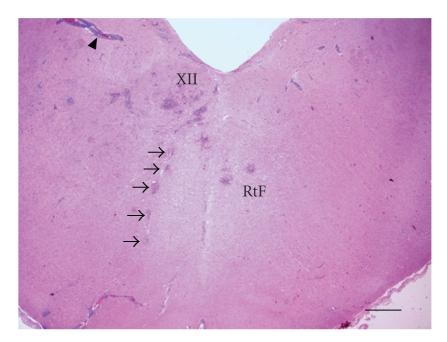

人类和反刍动物中由单核细胞增生李斯特菌引起的菱形脑炎:一种日益增多的人畜共患病?

Rhombencephalitis Caused by Listeria monocytogenes in Humans and Ruminants: A Zoonosis on the Rise?

Listeriosis is an emerging zoonotic infection of humans and ruminants worldwide caused by Listeria monocytogenes (LM). In both host species, CNS disease accounts for the high mortality associated with listeriosis and includes rhombencephalitis, whose neuropathology is strikingly similar in humans and ruminants. This review discusses the current knowledge about listeric encephalitis, and involved host and bacterial factors. There is an urgent need to study the molecular mechanisms of neuropathogenesis, which are poorly understood. Such studies will provide a basis for the development of new therapeutic strategies that aim to prevent LM from invading the brain and spread within the CNS.

摘要